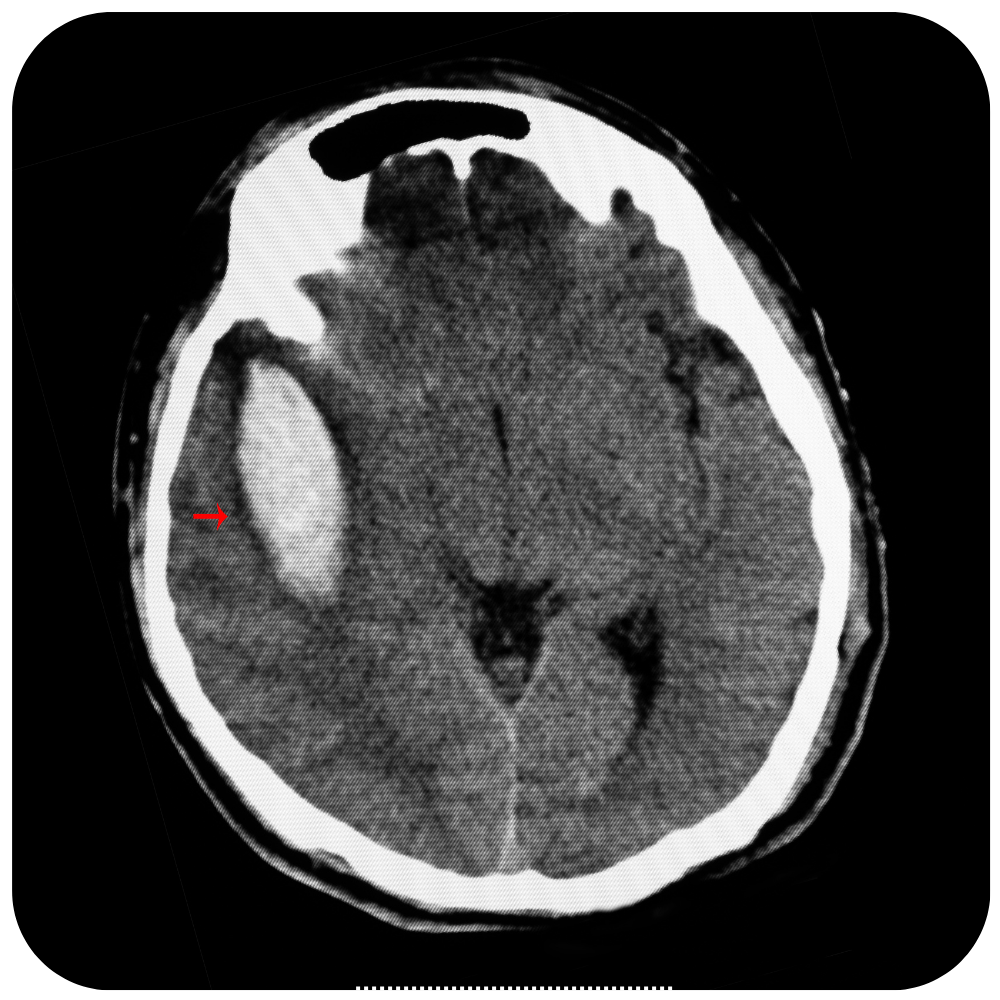

Craneotomía Operación en la que se extrae un pedazo del cráneo. Una craneotomía se realiza para que los médicos puedan extraer un tumor o tejido anormal del cerebro. También se puede realizar para extraer sangre o coágulos del cerebro, aliviar la presión en el cerebro después de una lesión o…